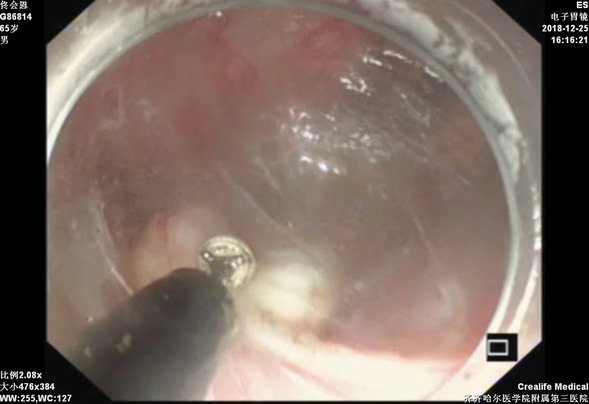

钛夹封闭隧道口